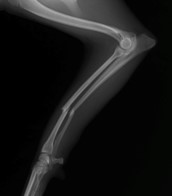

眼球摘出、眼瞼腫瘤切除、チェリーアイ整復、眼瞼縫合、瞬膜フラップ、眼球突出整復、耳介切除、垂直耳道切除、総耳道切除、鼻鏡切除、口腔腫瘍切除(上顎骨切除、下顎骨切除を含む)、各種抜歯(猫の全臼歯抜歯含む)舌腫瘍切除、唾液腺嚢胞切除、皮膚腫瘤切除、断脚(前肢、後肢、片側骨盤切除)、断尾、肺葉切除、胸腺腫切除、心膜切除、横隔膜ヘルニア整復、肝臓腫瘍切除、胆嚢摘出、胃切開、胃拡張胃捻転症候群整復、胃腫瘍切除、腸管切開、腸管腫瘍切除、直腸腫瘍切除(粘膜、全層プルスルーなど)、腎臓摘出、SUB設置手術、脾臓摘出、副腎摘出、膀胱切開、膀胱腫瘍切除(部分切除、全摘出、膀胱尿道一括切除など)、卵巣腫瘍切除、精巣腫瘍切除、卵巣子宮全摘出、肛門嚢切除、各種骨折、膝蓋骨脱臼整復、股関節脱臼整復、大腿骨頭切除、椎間板ヘルニア(各種椎弓切除術)、各種リンパ節切除 など